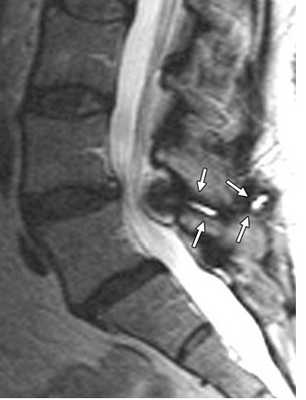

Дальнейшая дегенерация суставного аппарата приводит к ослабеванию связок и их кальцификации. Костные мосты между телами 4 смежных позвонков за счёт обызвествления передней продольной связки наблюдается у 15-20% взрослых. Уменьшение высоты диска приводит к смыканию остистых отростков. В результате образуются псевдосуставы, вокруг которых развивается гранулематозное воспаление. С остеоартрозом связан также дегенеративный спондилолистез. Обычно это антелистез 4 поясничного позвонка на 5. В отличие от других этиологий может быть и не только антелистез, но и ретролистез. Степень листеза всегда небольшая.

МРТ поясничного отдела позвоночника. Болезнь Бааструпа. Псевдосустав обозначен стрелками. Сагиттальная Т2-взвешенная МРТ.